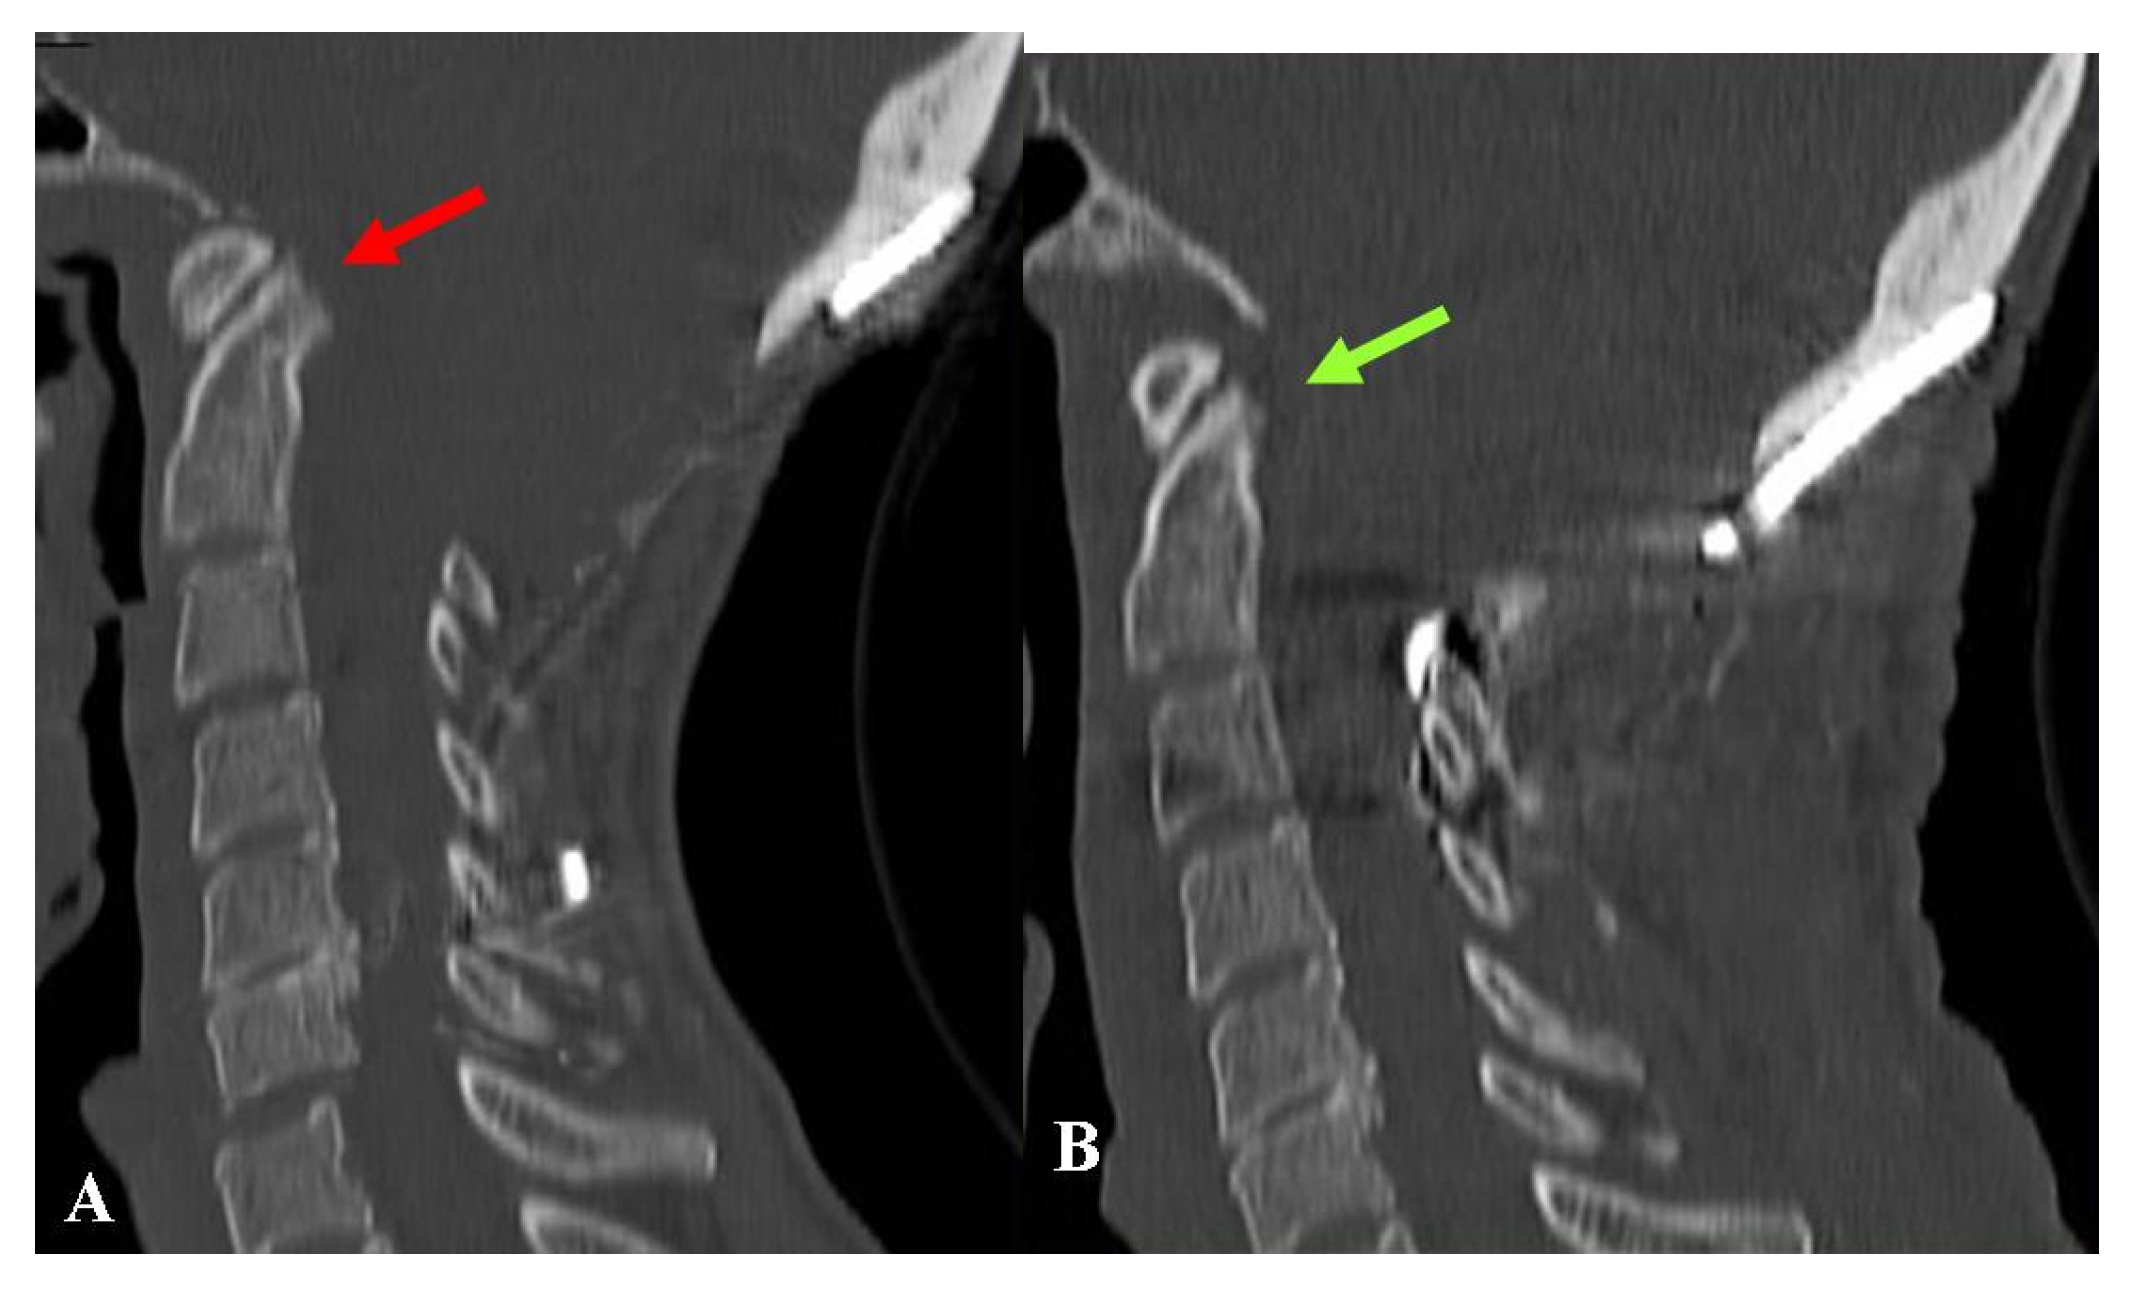

Another patient presented to us with severe dysphagia. She had been operated for FMD + DA plus occipito-cervical fixation. Repeated imaging studies documented ventral bulbar compression by basilar impression. The clivo-axial angle was below 135°. The treatment consisted of removal of the fixation device followed by cranial traction under general anesthesia with muscle relaxation under continuous radiologic and neurophysiologic monitoring. This enabled the basilar impression to be reduced. The reduction was maintained by placing a new craniocervical fixation (Figure 6).

Regarding the patient with craniocervical fixation and basilar impression (Figure 6), postoperative assessments demonstrated an adequate reduction in the bone malformation. Although her swallowing disturbances improved, one year later she still complained of severe headache and asthenia. The final CCOS score was 10 and her QOL was unchanged.

Figure 6. This 43-year-old woman had undergone osteodural decompression and craniocervical fixation. Six months later, she was referred to us due to progressively worsening swallowing disturbances, severe weight loss, asthenia, and marked continuous occipital pain. (A) Preoperative CT-scan, sagittal reconstruction showing a relatively wide bone decompression and a basilar impression with a quite acute clivo-axial angle (red arrow). Under neurophysiologic and radiologic monitoring, the patient underwent the removal of the fixation device and cranial traction. The basilar impression could be reduced, which made the planned procedure of odontoidectomy unnecessary. New craniocervical fixation devices were placed to maintain the new position. (B) Follow-up CT-scan, sagittal reconstruction, obtained one year later, showing resolution of the basilar impression (green arrow). The swallowing problems almost completely went away, and the headache got better, but the asthenia stayed. The final CCOS score was 10.